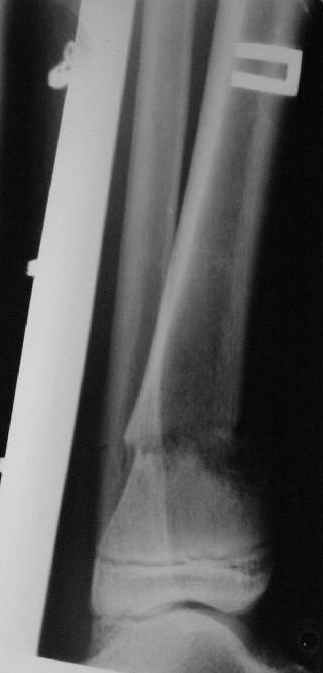

Операции: 1 Клиновидная резекция на вершине деформации м\берцовой кости.

2 Тугоподвижный ложный сустав н\3 б\берцовой кости. Рубцы выполняющие пространство между отломками, канал проксимального отломка иссечены.

Одномоментное устранение деформации, остеосинтез Г-образной пластиной.

Пластика по Хахутову.

Заживление проксимальной части раны вторичным натяжением без нагноения. Рана зажила. Спицы удалены через 1,5 недели после операции.

Промежуточный

|